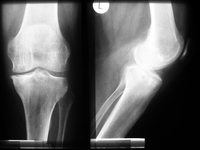

Teilprothese oder Schlittenprothese

Bei diesem Prothesenmodell wird nur der geschädigte innere, selten äußere Teil des Kniegelenkes ersetzt. Voraussetzung ist, dass eine Gelenkhälfte und das Kniescheibengelenk intakt sind, und stabile Bänder ohne höhergradige Bewegungseinschränkung vorliegen. Häufig wird diese Teilprothese bei isoliertem innenseitigen Knieverschleiß eingesetzt.

Das deutlich kleinere Implantat im Vergleich zur Vollprothese ermöglicht weichteilschonende Operationstechniken und kleinere Zugänge sowie einer schnellere Rehabilitation.